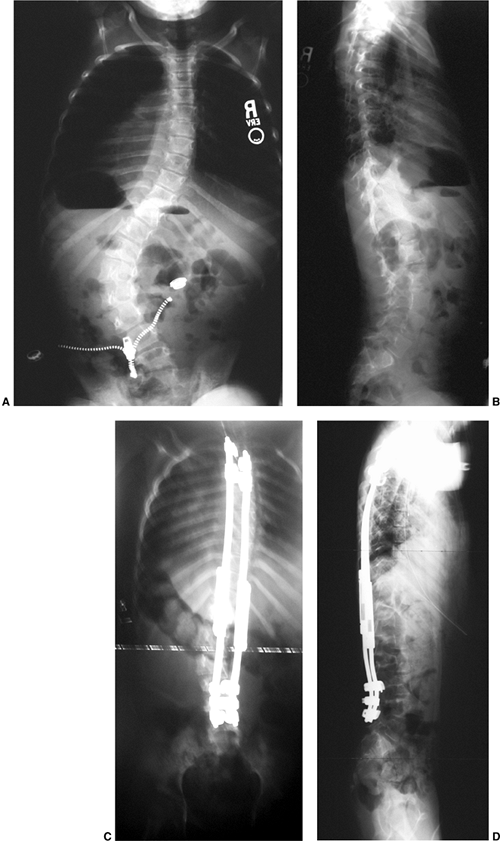

![]()  |

Figure 18.17 A:

This 4-month-old baby boy presented with a left thoracic scoliosis. A magnetic residence imaging (MRI) study was performed and found to be normal. He was therefore diagnosed with infantile idiopathic scoliosis. The rib vertebral angle difference was greater than 20 degrees, suggesting likely progression. B: At 3 years 2 months of age, after substantial progression and multiple attempts at casting, his curve has continued to increase with substantial chest wall deformity. C: At 9 years 2 months his curve has progressed to a severe degree. This was despite attempts at bracing, as well as subcutaneous growth rodding. His growth rods required removal after several years because of infection. This demonstrates the challenges of treating progressive infantile idiopathic scoliosis.  |